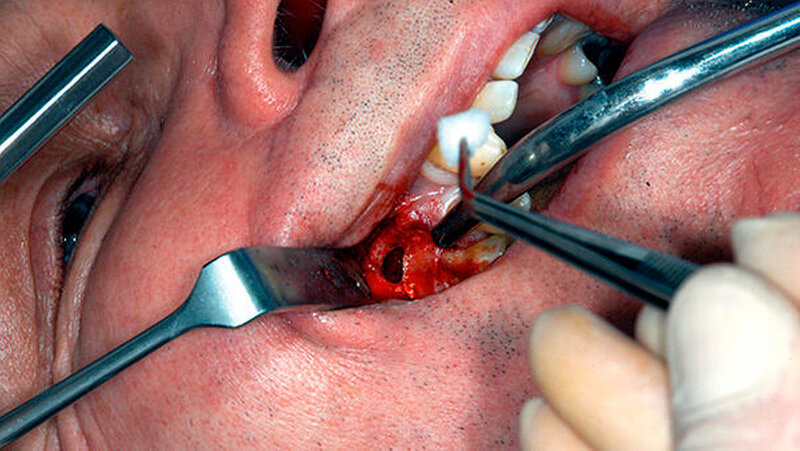

Mit einem ultraschallgetriebenen diamantierten, abgewinkelten Instrument wurden beide Wurzelkanäle der mesiobukkalen Wurzel von retrograd präpariert (Abbildung 3). Das frakturierte Instrument konnte so dargestellt (Abbildung 4) und entfernt werden.

Beide mesiobukkalen Wurzelkanäle wurden mit einem Ultraschallansatz etwa 3 mm tief von retrograd präpariert und gesäubert. Biodentine (Septodont) wurde als retrogrades Wurzelkanalfüllmaterial gewählt, nach Herstellerangaben angemischt und retrograd appliziert (Abbildung 5). Der mukogingivale Lappen wurde adaptiert und vernäht. Das postoperative Röntgenbild zeigte eine vollständige Entfernung des frakturierten Instruments sowie einen Knochendefekt um die mesiobukkale Wurzelspitze herum (Abbildung 6).